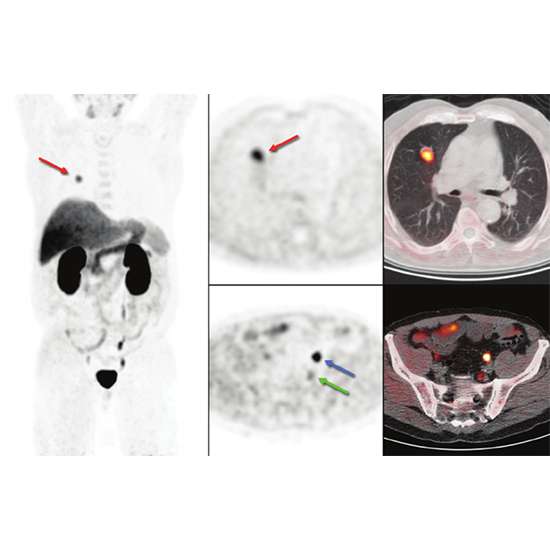

18F-choline positron emission tomography also known as also known as F-18 Choline PET scan is a latest and highly advanced diagnostic tool in nuclear imaging which is used for detection and evaluation of certain cancers especially prostate cancers.

Choline is a constituent of phospholipids, an essential component of cell membrane. Rapidly dividing cancer cell requires choline for cell membrane synthesis. Thus, Radio-labelled F-18 choline is used as a radiopharmaceutical agent in PET scanning and its increased uptake is usually demonstrated by cancerous tissues.

F-18 Choline PET scan is usually combined with CT scan to obtain functional, biochemical and anatomical details of cancers in the same session. It provides images with greater clarity and higher resolution for better identification and evaluation of the underlying pathological condition.

2) Secondary metastases to distant sites such as lymph nodes, bone, soft tissues or distant viscera.

5) Your radiologist may perform a dual phase protocol for prostate cancer evaluation in which immediately after a radiotracer injection, a static acquisition of your pelvis is obtained which is followed by a whole body scan after 1 hour of intravenous radiotracer.